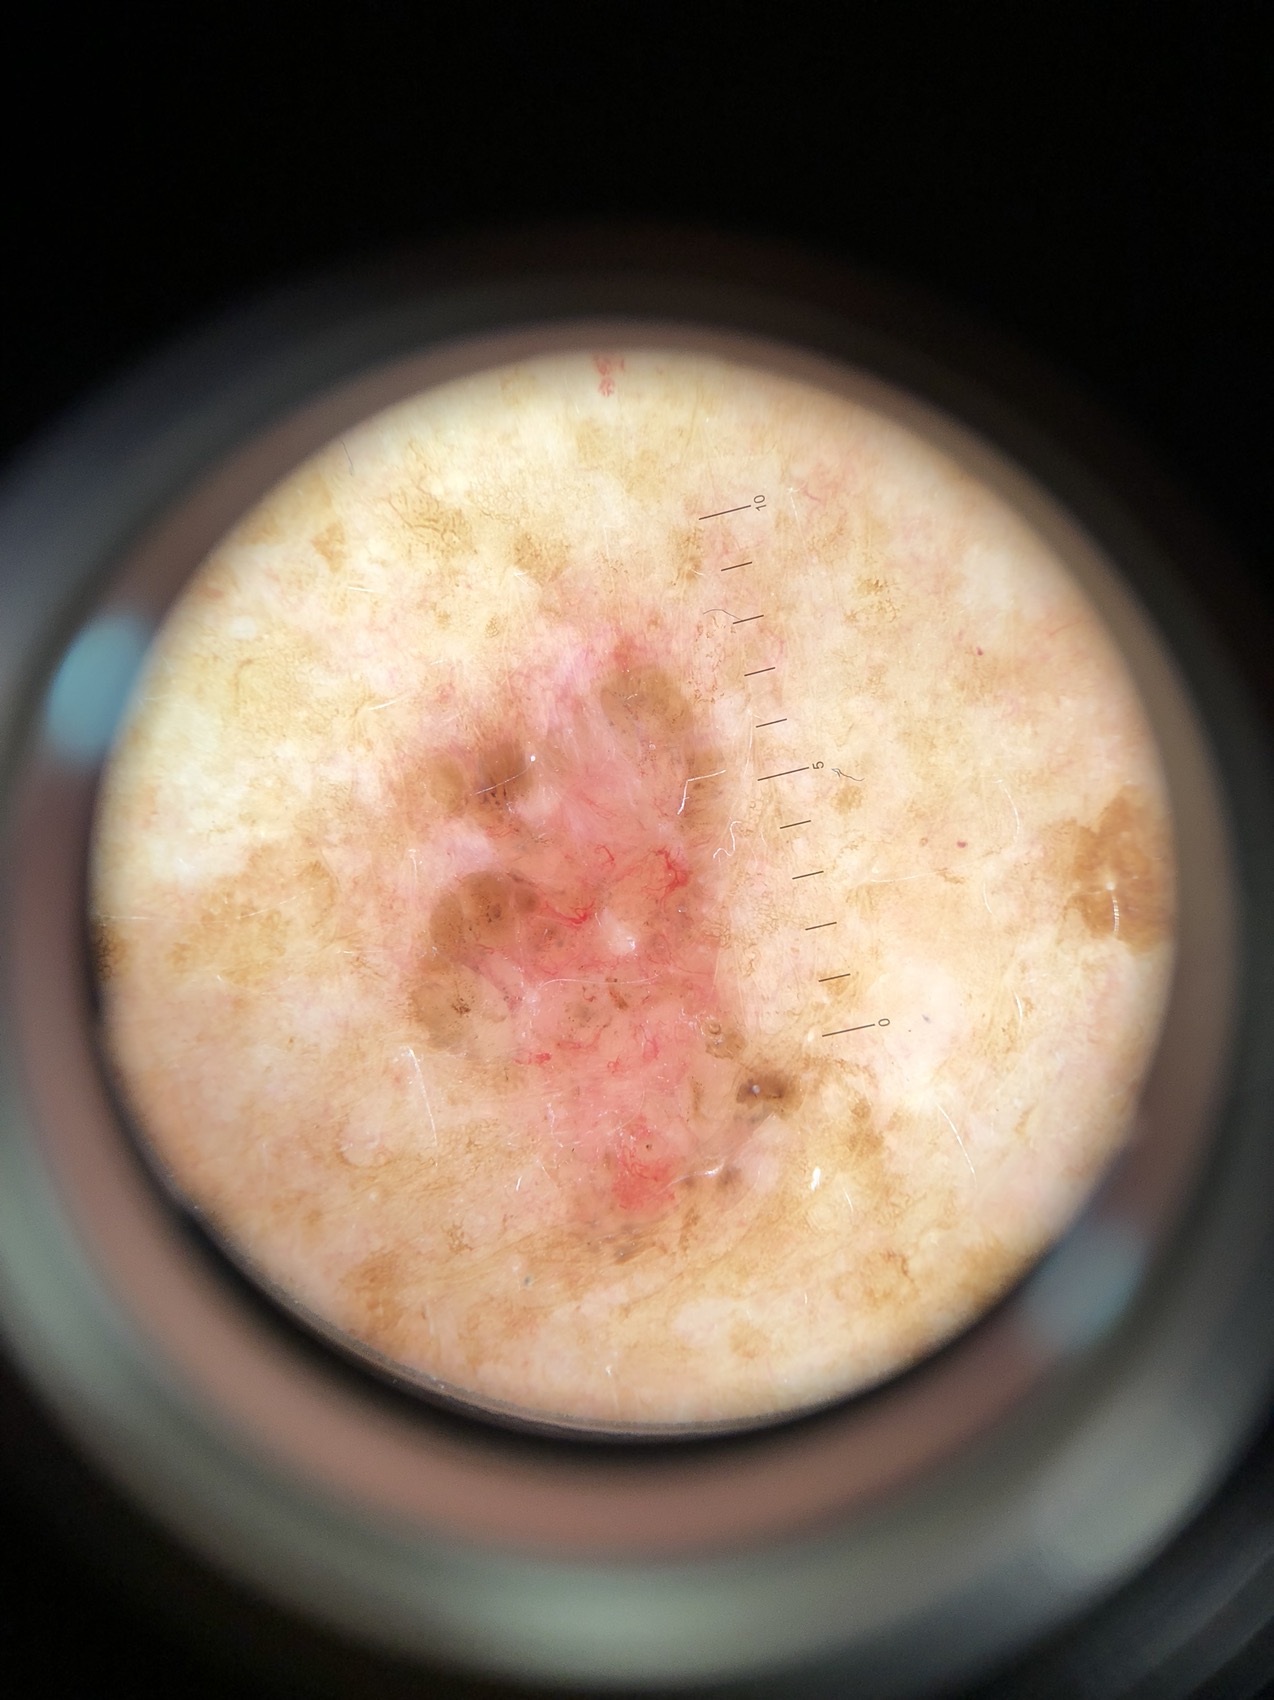

Seuraavana muutamia luomikuvia ja heti perään valokuva joka otettu dermatoskoopin kautta. Testaa itsesi jos tunnistat ko. muutokset!

Potilas 5, yläselässä kaksi punoittavaa muutosta jotka eroavat rasvasyylistä:

Potilas 5: yläselässä kaksi erillistä basalioomaa eli tyvisolusyöpää.